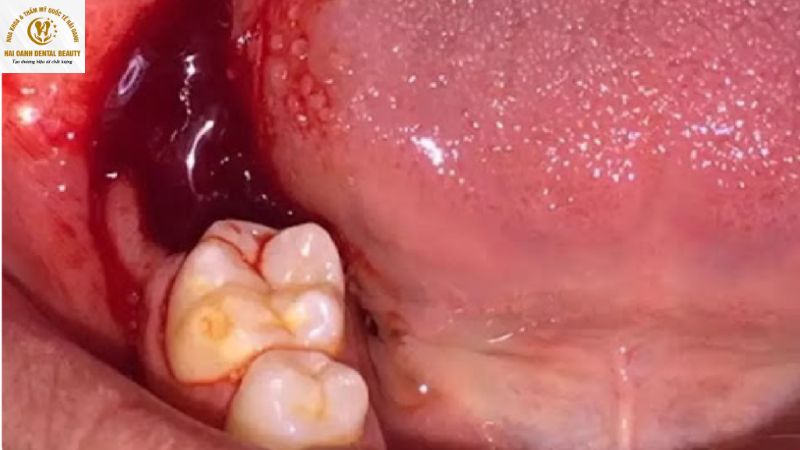

- Chảy máu bất thường: Sau khi nhổ răng, máu sẽ đông và ngừng chảy sau 30 - 60 phút. Nếu máu tiếp tục rỉ ra hoặc chảy nhiều không ngừng trong nhiều giờ, bạn cần tìm sự trợ giúp y tế ngay lập tức.